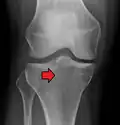

Lipohemarthrosis (presence of fat and blood from bone marrow in the joint space after an intraarticular fracture) seen on X-ray in a person with a subtle tibial plateau fracture -

Lipohemarthrosis due to a tibial plateau fracture -

Subtle tibial plateau fracture on an AP X ray of the knee -

A tibial plateau fracture seen on X-ray